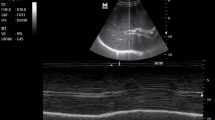

Sonographic assessment of diaphragm

Sonographic assessment of the diaphragmatic motion and contraction was performed before blockade and after surgery according to the “ABCDE” method described by Tsui et al.18. The “ABCDE” method is performed by placing the probe at the zone of apposition of anterior Axillary line, watching for Breathing (lung sliding), then moving Caudally to identify the Diaphragm for Evaluation. During full inspiration and breath holding at total lung capacity, thickening of the diaphragm observed under sonography indicates that the diaphragm is shortening and contracting. The diaphragm thickening fraction (DTF) is calculated as: (thickness at inspiration − thickness at expiration)/thickness at expiration (Fig. 2).

In this study, the primary outcome was the incidence of HDP, defined as less than 20% of DTF on M-mode ultrasound19. Complete and partial hemidiaphragmatic paralysis were defined as less than 5% of DTF (or the paradoxical movement of diaphragm), and between 5 and 20% of DTF, respectively.